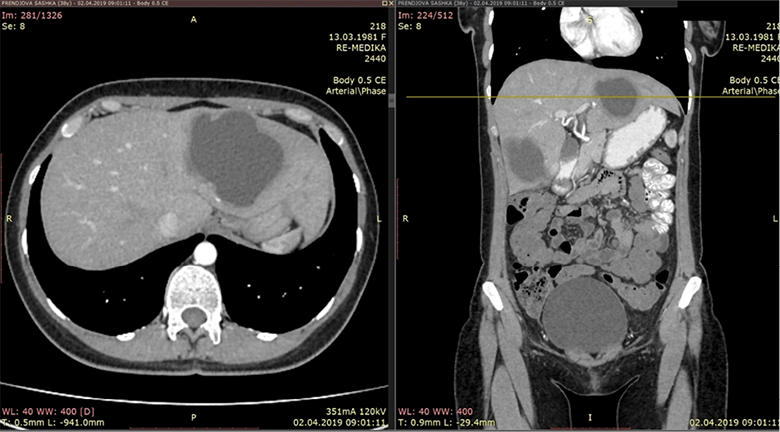

An CT scan of the abdomen was performed and were found two cystic liver formations, also a cystic formation was verified in the pelvis. The native series of the abdominal CT have shown a segment II and IV hepatic per-magna cystic formations with dimensions: No I: 80×60×74 mm (Figure 1) and No. II: 70×60×58 mm (Figure 2). The changes are with a pericystic reaction of a hypodense character. The formation in the second hepatic segment had a visible mass effect on the stomach. In post contrast series, cystic liver formations were shown as hypodense, hypovascular structures with a clearly expressed contrast accumulation in the cystic membrane and with a demarcation of the pericystic reaction. Per magna cystic formation with hypodense character was also detected at the level of the small pelvis, retrouterine, in the Douglas space, with dimensions of 93×90×62 mm (Figure 3). The cyst has a clearly expressed mass effect on surrounding organ structures. Utter in the AVF pressed to the left. The liver cystic formations were with characteristics of Ehcinococcal cyst but with no serological verification.

Figure 1. Liver segmet II permagna cystic formation

Figure 2. Segment IV hepatic cystic formation

Figure 3. Hypodense cystic formation in small pelvis